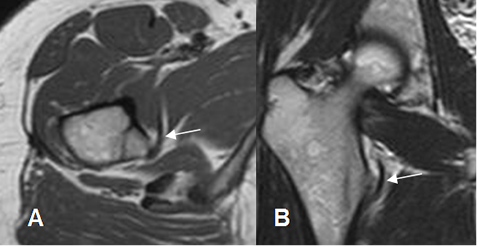

En la ArtroRM, es importante no confundir el ligamento redondo, con un cuerpo libre. (8). (Fig 26).

Fig 26. Ligamento redondo normal.

A: ArtroRM coronal y B: ArtroRM axial. Estructura hipointensa medial a la cabeza femoral, que corresponde al ligamento redondo.